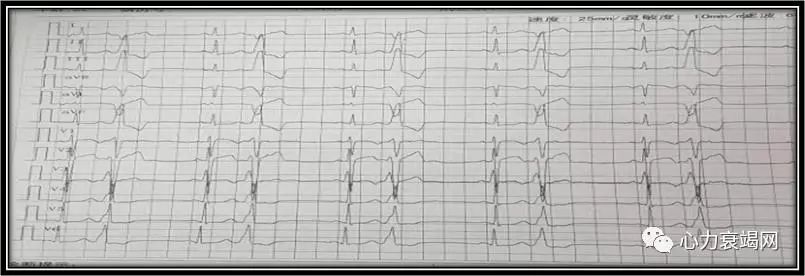

➤ ECG:

室早二联律(右室流出道起源),QTc间期456 ms

窦性心动过缓、窦性停博(R-R间歇2.2s)、频发多形性室早、QT间期延长(QTc:572)